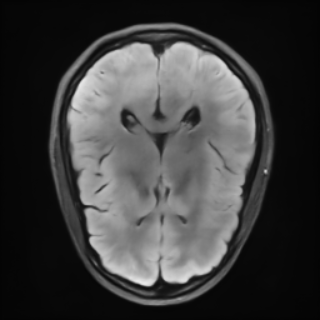

This article presents a novel undersampled magnetic resonance imaging (MRI) technique that leverages the concept of Neural Radiance Field (NeRF). With radial undersampling, the corresponding imaging problem can be reformulated into an image modeling task from sparse-view rendered data; therefore, a high dimensional MR image is obtainable from undersampled $k$-space data by taking advantage of implicit neural representation. A multi-layer perceptron, which is designed to output an image intensity from a spatial coordinate, learns the MR physics-driven rendering relation between given measurement data and desired image. Effective undersampling strategies for high-quality neural representation are investigated. The proposed method serves two benefits: (i) The learning is based fully on single undersampled $k$-space data, not a bunch of measured data and target image sets. It can be used potentially for diagnostic MR imaging, such as fetal MRI, where data acquisition is relatively rare or limited against diversity of clinical images while undersampled reconstruction is highly demanded. (ii) A reconstructed MR image is a scan-specific representation highly adaptive to the given $k$-space measurement. Numerous experiments validate the feasibility and capability of the proposed approach.